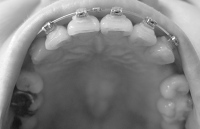

奥に引っ張るのは前歯の隙間を詰めてからにするとかなんとか言い出して、ワイヤー交換して前の歯にパワーチェーン(だと思う)を付けて終了。

しかもワイヤーをもう一段太くしようとして、ブラケットに無理やり押し込んで抜けなくなり、顎をギシギシいわせながらぐいぐい引っ張られました。以前にも同じことやってんのよね、この先生。

その後、何事もなかったようにワイヤーを付け始めたので抜けたのか?と思っていたのですが、終わってから見てみたら、刺さったワイヤーはそのままで、交換したワイヤーがブラケットに細い針金で固定されてました

まぁほんまに、ないんやろうけどなぁ。奥に引っ張るのは前歯の隙間を詰めてからにするとかなんとか言い出して、ワイヤー交換して前の歯にパワーチェーン(だと思う)を付けて終了。